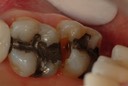

Alan Tamashiro #31 pre-op

Alan Tamashiro #31 amalgam removal